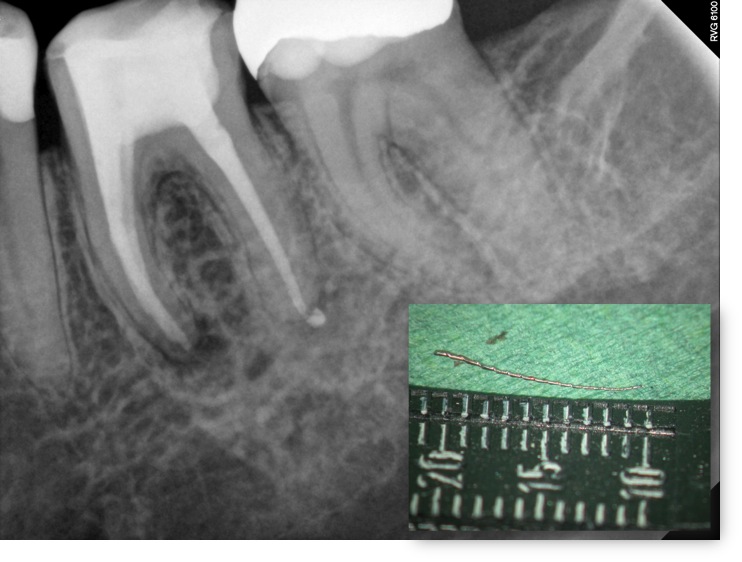

Fragmentchir